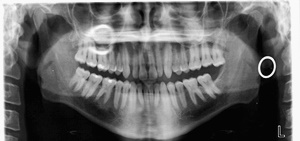

우리가 사랑니라고 부르는 것은 큰 어금니 중 세 번째 위치에서 제일 마지막에 나오는 치아입니다. 사랑니가 나올 때에는 첫사랑을 하듯이 아프다고 하여 붙여진 이름이라고 하는데요. 다른 이름으로는 ‘지치’라고 합니다. 지치는 사리를 분별할 수 있는 지혜가 생긴다는 뜻입니다.

사랑니는 보통 큰 어금니와 비슷하게 생겼습니다. 사랑니의 형태나 크기는 매우 다양하다고 하는데요. 보통의 어금니 보다 깊이 나기 때문에 빼기 어렵거나 절개를 통해 힘들게 빼야 하는 경우가 많습니다. 원래 사랑니는 음식물을 갈아 내기 위한 용도라고 하는데요. 이것은 치아의 퇴화 현상이라고 생각하시는 분들도 많이 계십니다.